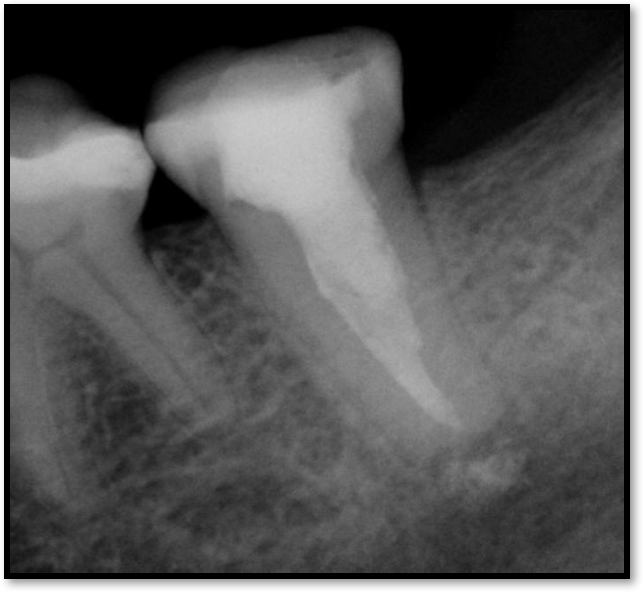

Figure 2 shows a situation where the clinician excavated the tooth of a patient with decay, and it pulped out. The buccal and lingual walls were intact; however, the walls were minimal, and there were still fragments of amalgam and cracks. If the clinician prepared this tooth after building it up, the clinician would lose all the good tooth structure that was left. This tooth would likely need a post.

Fig 2. Minimal walls.

Figure 2